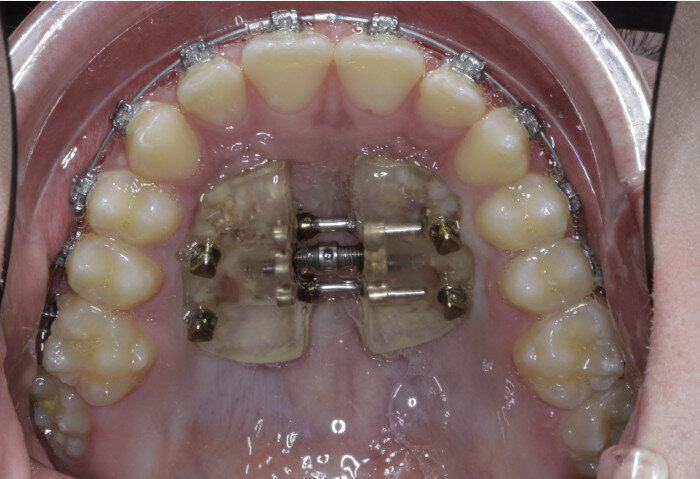

Case 5: Skeletal expansion

In cases where absolute maxillary expansion is desired with little to no dental side effects, maxillary anchorage with TADs is a wonderful solution. This allows for sutural expansion that has little to no dental compensation. Many designs exist for TAD placement with expansion. In some cases, a tissue-borne expander is used with no anchorage on the molars. This is typically used to encourage the maximum amount of skeletal expansion when dental tipping is undesired (Figs. 52 & 53). In cases where molar anchorage is desired, a banded approach can be used in conjunction with TADs (Figs. 54–59).

Fig. 54

Fig. 55